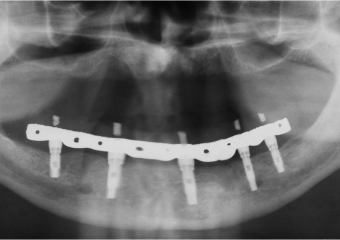

Raio X com 05 Implantes Instalados